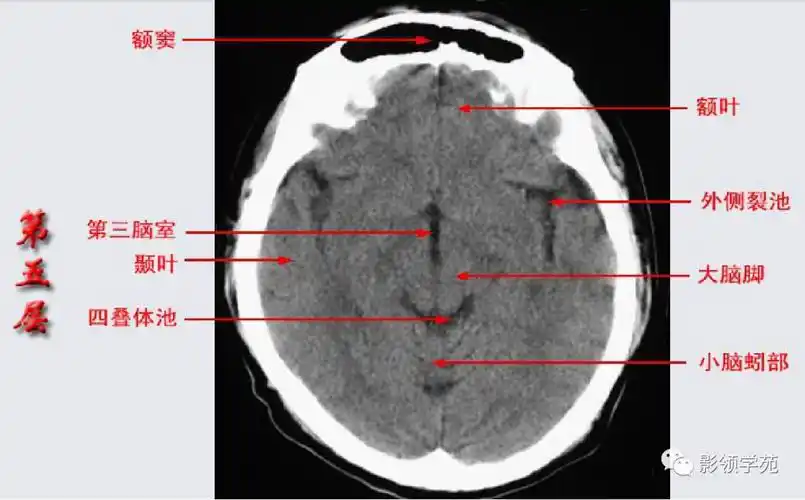

头部ct影像解剖